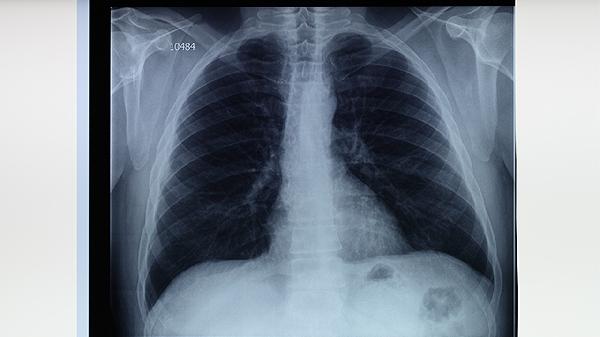

治療期間每月需進(jìn)行痰涂片、胸部X線檢查,評(píng)估藥物療效。完成療程后每3-6個(gè)月復(fù)查1次,持續(xù)2年。肝功能異常者需增加檢測(cè)頻率,使用乙胺丁醇片者應(yīng)定期檢查視力。復(fù)查可及時(shí)發(fā)現(xiàn)復(fù)發(fā)或藥物不良反應(yīng)。